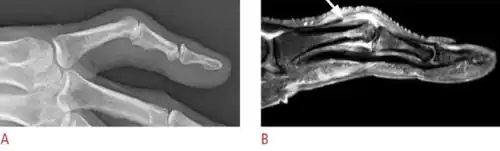

| Boutonniere deformity in a person with rheumatoid arthritis | |

Boutonniere deformity is a deformed position of the fingers or toes, in which the joint nearest the knuckle (the proximal interphalangeal joint, or PIP) is permanently bent toward the palm while the farthest joint (the distal interphalangeal joint, or DIP) is bent back away (PIP flexion with DIP hyperextension). Causes include injury,[1] inflammatory conditions like rheumatoid arthritis, and genetic conditions like Ehlers-Danlos syndrome.[2]